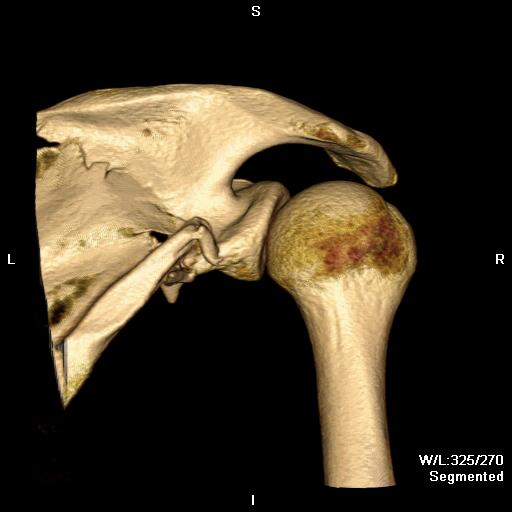

Combined Glenoid and Scapula Fractures

Case 1

- displaced glenoid fracture and neck fracture

- ORIF both through posterior / Judet approach